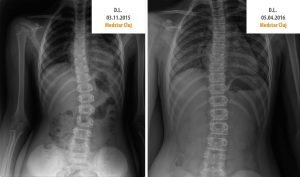

Rezultatele Terapiei Schroth

Aplicată sub atenta îndrumare a unui kinetoterapeut, terapia Schroth dă rezultate remarcabile. În imaginile de mai jos puteți observa cum,...